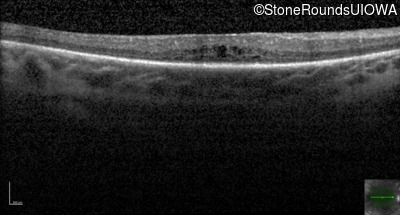

Optical Coherence Tomography - Left - 20/70 +1

Exemplar / OCT Stack